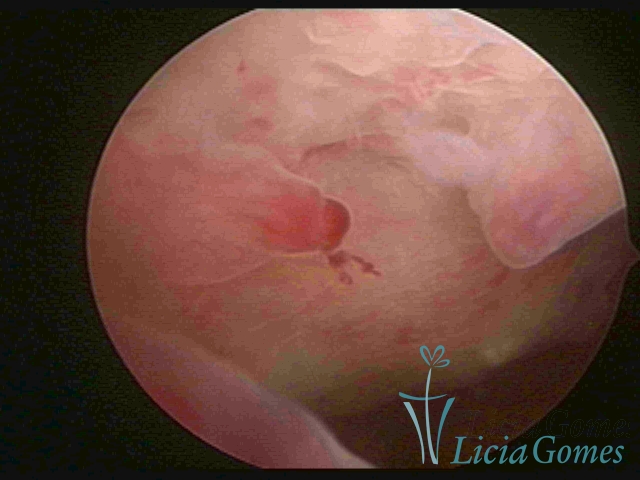

A Hiperplasia Complexa tem um aspecto pseudo polipoide, lembrando tecido cerebroide ou com reação deciduoide. A vascularização superficial é mais evidente e com vasos em formatos de saca-rolha ou espirais.

A Hiperplasia atipia e o aspecto histeroscópico são semelhantes à da hipertrofia complexa, visualizando também a vascularização com atipias. Com o aumento do calibre dos vasos superficiais, pode ser encontrado também tecido em necrose.